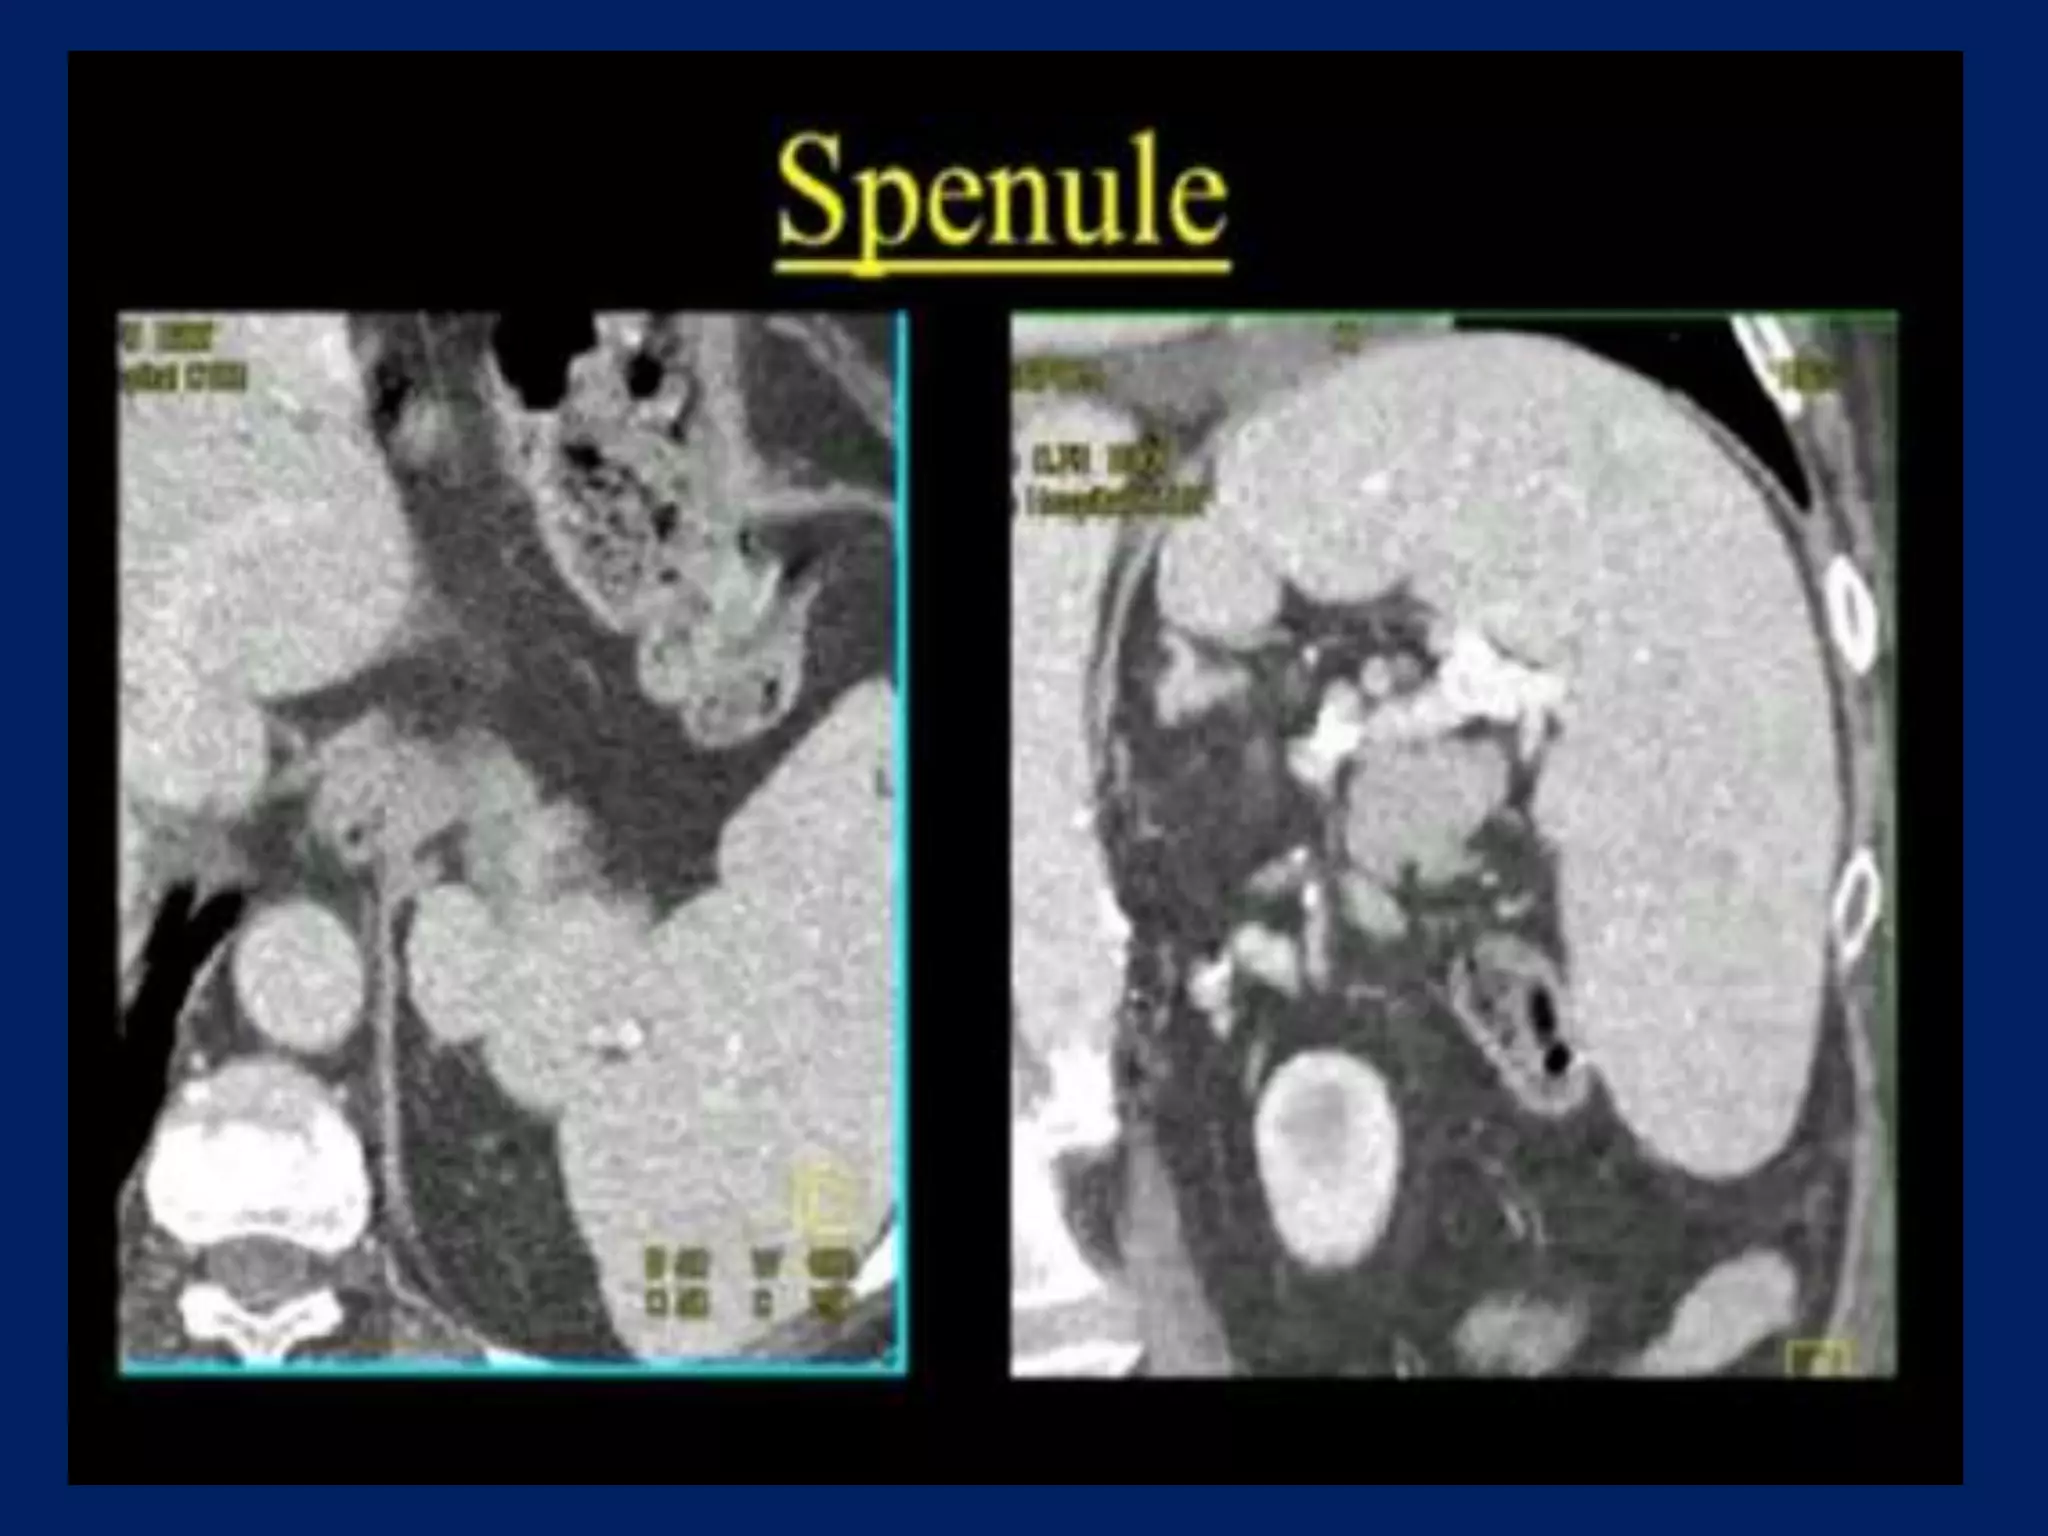

This document discusses imaging of the spleen and summarizes various congenital anomalies and pathologies that can affect the spleen. Some common congenital anomalies mentioned include accessory spleens, asplenia, polysplenia, and splenic fusions. Acquired conditions like repeated infarctions, infiltration, tumors, and cysts can also cause splenomegaly or functional asplenia. Wandering spleen is discussed as a rare congenital anomaly where the spleen lacks attachments and is mobile within the abdomen. Various grades of splenic lacerations and examples of splenic imaging findings are also briefly summarized.